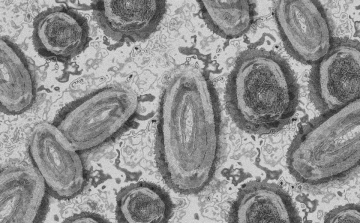

Tovább nőtt a majomhimlő-fertőzöttek száma Magyarországon

Újabb két embernél igazolt majomhimlő-fertőzést a Nemzeti Népegészségügyi Központ (NNK) a 33. héten - augusztus 15-től 21-ig -, ezzel 64-re nőtt a magyarországi esetek száma.

Egy 3 év alatti gyermek fertőződött meg majomhimlővel Belgiumban

Belgiumban egy 3 év alatti gyermek fertőződött meg majomhimlővel - számolt be róla szerdán a Sudinfo hírportál.

Megfertőződött a majomhimlővel egy gyerek Németországban

Megfertőződött majomhimlővel egy négyéves kislány Németországban - jelentették kedden német hírportálok az országos közegészségügyi intézet (RKI) adatai alapján.